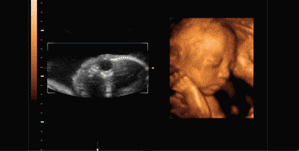

四维彩超是目前世界上最先进的彩色超声设备,是采用三维超声图像加上时间维度参数,更直观更清晰地呈现胎儿在宫内的动态图像,多方位、多角度地观察胎宝宝的生长发育情况,还能够对孕期潜藏的各类疾病进行精确检测。